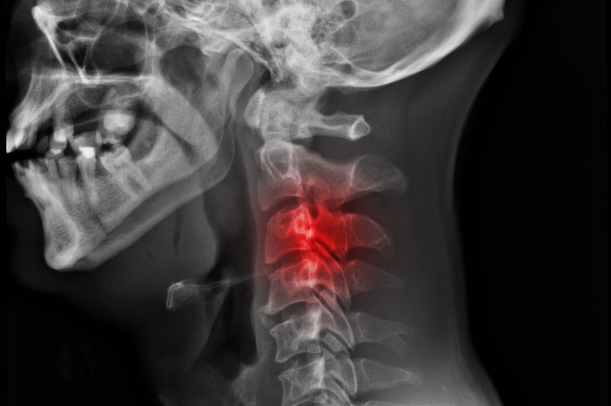

医療機関での診断基準(レントゲン等)

セルフチェックで違和感を覚えた場合や症状が続くときは、医療機関での確認も選択肢の一つになると言われています。整形外科などではレントゲン検査を行い、頸椎の角度を測定することで前弯がどの程度失われているかを確認できると説明されています(引用元:https://kumanomi-seikotu.com/blog/3238/)。

また、筋肉や神経の状態を触診で確かめ、必要に応じて追加の検査を行う場合もあるとされています。